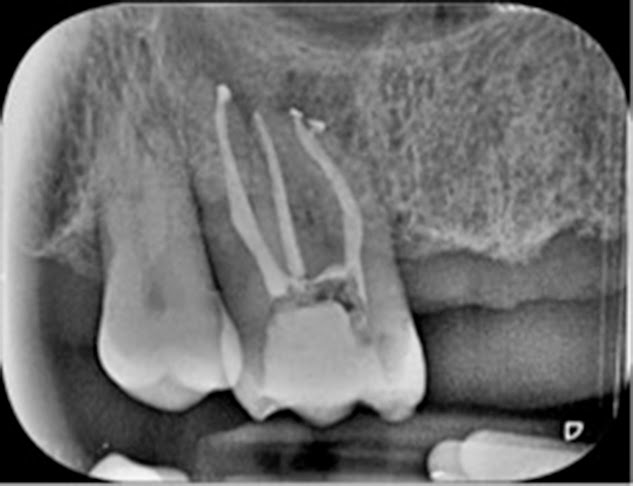

Acude al Master

un paciente de 49 años de edad, sin antecedentes médicos de interés y con

molestias a la masticación en el segundo cuadrante.

Como pruebas

diagnósticas, por un lado, el 27 presenta

sensibilidad -, movilidad –, percusión + y palpaciónPor otro lado,

el 28 presenta sensibilidad +, movilidad -, palpación - y percusión – . Ambos dientes presentan pérdida osea debido a enfermedad periodontal.

Modificamos la apertura con la punta de ultrasonidos y eliminamos la

gutapercha con protaper f2 sin necesidad de recurrir al eucaliptol. Localizamos

los conductos con el localizador de ápices Raypex 6 e instrumentamos

con Protaper S1, S2 a LT y Profile 25.06/30.06 a LT. Parece que se

insinua el MP, pero tras utilizar el ultrasonidos y el microscopio no se

localizó; en MV sobrepasamos el escalón con limas manuales 08, 10, 15 e irrigamos entre

lima y lima durante toda la intrumentación con NaOcl 5,25%. Las longitudes de trabajo fueron:

MV: 19 mm, DV: 20 mm y P: 21 mm; y la LAM

de todos 40.